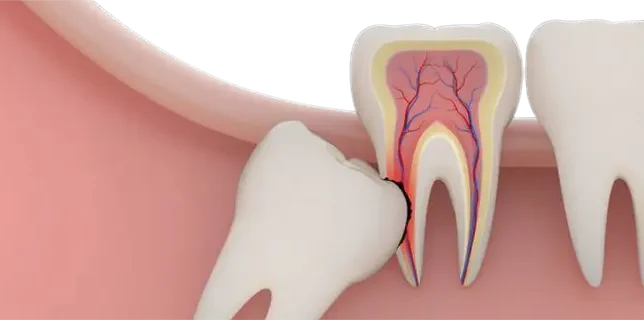

When a tooth is extracted, the bone that once surrounded the tooth can begin to resorb (break down) over time. This is particularly common after wisdom teeth removal, especially if the teeth were impacted (not fully erupted) or if the extraction site is large. A bone graft helps fill the empty space left behind, preventing the bone from shrinking or deteriorating. This is important because maintaining the bone density and structure of your jaw helps preserve its shape and functionality.

2 Bone Grafts